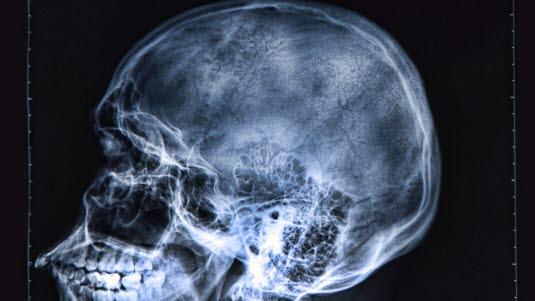

Mistenk alltid en ryggmargsskade hos en person som har pådratt seg en kraftig hodeskade. Illustrasjonsbilde: Colourbox

Et tungt slag mot hodet kan medføre blødning på innsiden av skallen eller hevelse i de skadete delene av hjernen.